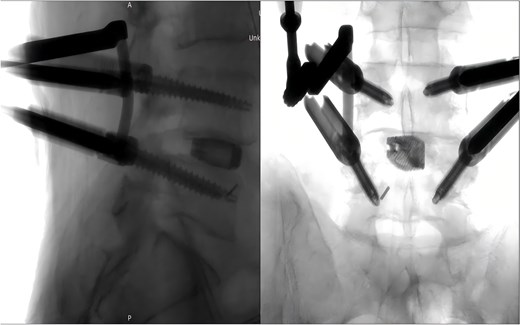

Following removal of the left L5 pedicle screw during the procedure, the smallest endoscopic sheath was inserted along with the endoscope to explore the screw trajectory. Under fluoroscopic guidance, endoscopic forcep was utilized to identify and grasp the fractured guidewire (Fig. 4). Tactile feedback of a metallic sensation confirmed precise localization. Approximately 6 mm of the fractured guidewire was successfully extracted (Fig. 5). Subsequent fluoroscopy confirmed complete removal of the broken guidewire. The left L5 pedicle screw was reinserted, and bilateral connecting rods were placed. The nuts were then securely fastened. Hemostasis was confirmed under endoscopic visualization, and the surgical incisions were closed and dressed with sterile coverings.

Following the surgery, the patient remained in stable condition with no reported discomfort. Postoperative radiographs verified complete extraction of the guidewire, with no residual fragments observed at the fracture site (Fig. 6). The patient experienced an uneventful recovery, and subsequent follow-up evaluations demonstrated satisfactory outcomes.

Postoperative anteroposterior and lateral radiographs of the lumbar spine.